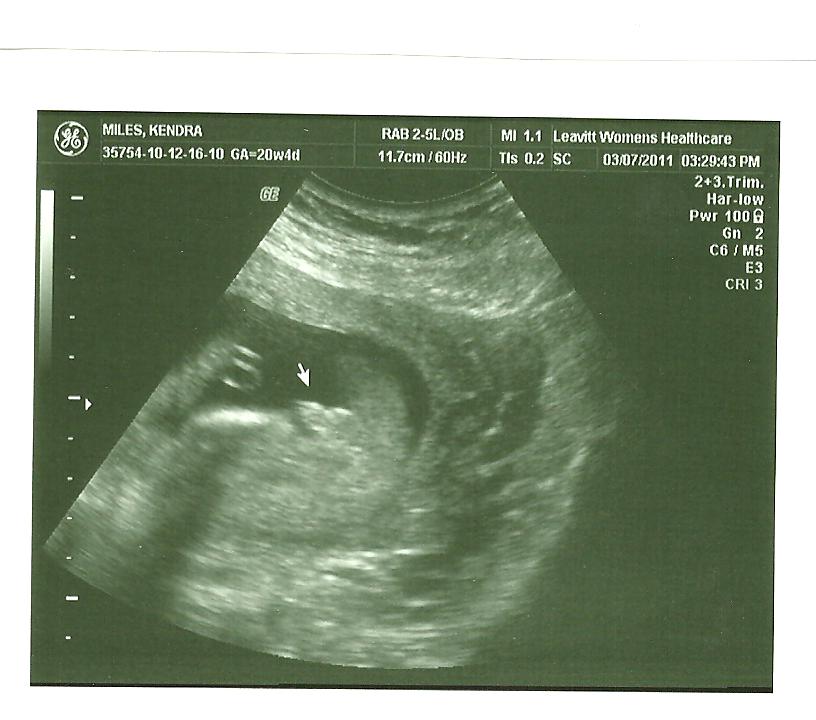

Miles Baby #4 Is A Boy!

Here are a few of the better pictures we got of our little guy. The first one is my favorite of his little foot it is so cute and a perfect shot. Then a little profile shot he had his hand up by his little mouth. You can't see much in the third one except for his spine but kind of a neat picture. The forth is the better picture we got letting us know that he is a little boy! We are so excited to have this little guy join our little family. You can't get the smiles off of daddies or Ethan's face when you talk about this little guy!